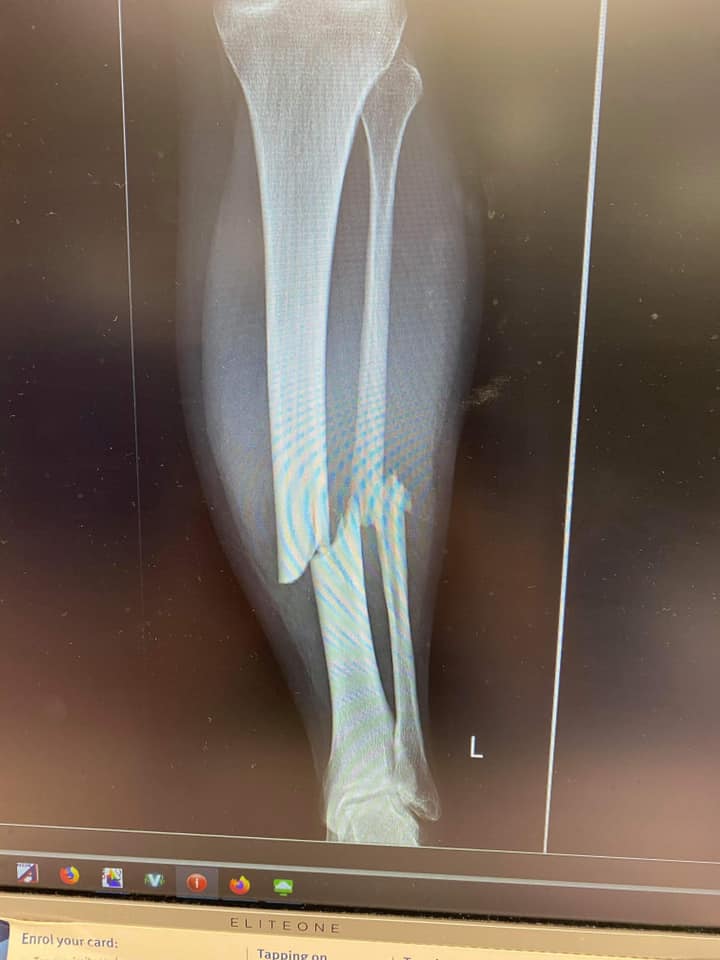

Only 10 months ago, discus thrower Taryn Gollshewsky's Olympic dream was shattered when she broke her leg playing soccer in the lead up to Tokyo.

The 29-year-old was sensationally sidelined from Olympic preparations when she broke her leg during a soccer match in the Wide Bay.

"With discus I am rotating, and I am twisting – so with the torque and the rotational forces that go through my leg, I was at risk of re-breaking my leg," Ms Gollshewsky said.